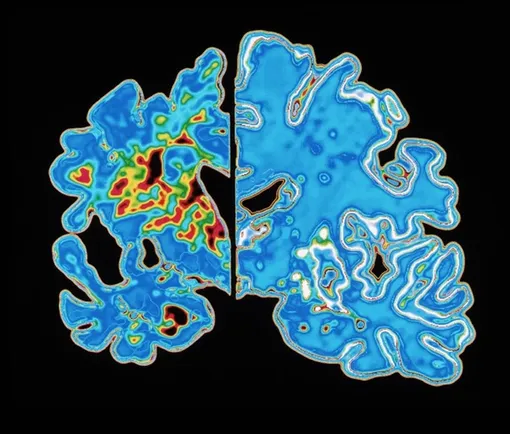

Анализ крови может предсказать начало болезни Альцгеймера

В ходе наблюдения за 600 пожилыми участниками исследования ученые заметили, что уровень этого белка растет с постоянной скоростью у разных людей. Это позволило создать математическую модель, которая, учитывая возраст пациента и концентрацию p-tau217, вычисляет примерную дату проявления заболевания с погрешностью в три-четыре года. Подобный подход превращает обычный анализ крови в своеобразные «молекулярные часы», отсчитывающие время до начала дегенеративных процессов в мозге. Работа опубликована в журнале Nature Medicine.